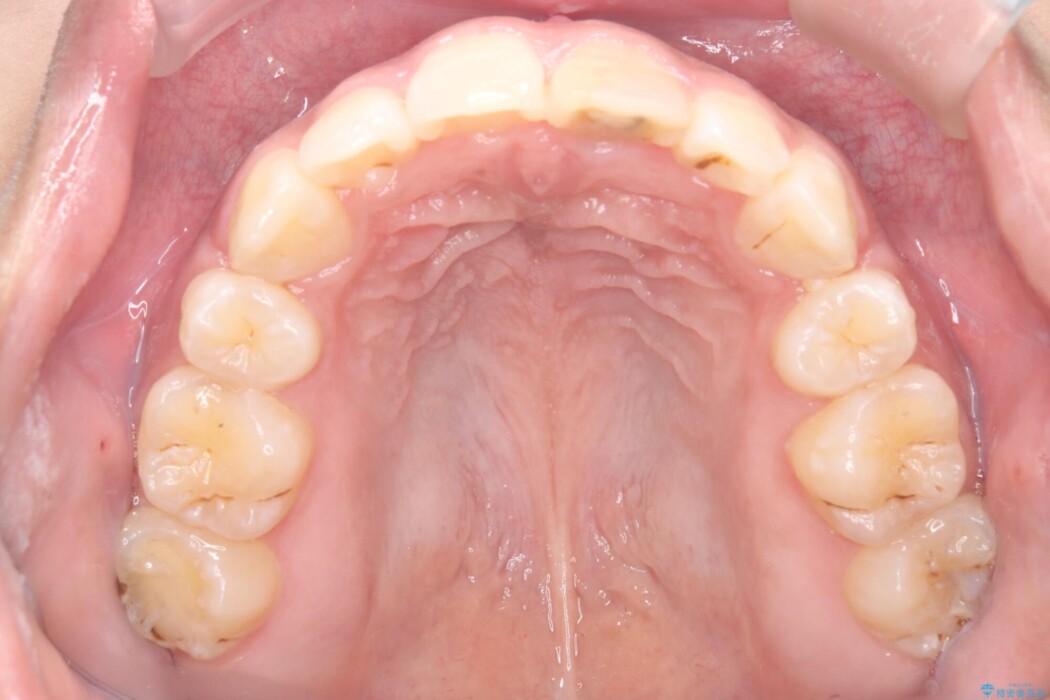

矯正検査の結果、歯列全体のスペースが不足しており、これが突出感の原因となっていました。

無理に歯を並べても口元の突出感は解消されないため、上下左右4番を抜歯しスペースを確保、目立ちにくい審美ワイヤー装置にて治療を行うこととしました。

抜歯によって得たスペースを活用し、審美ワイヤーによる繊細な角度調整を行いながら前歯を後方へ移動。